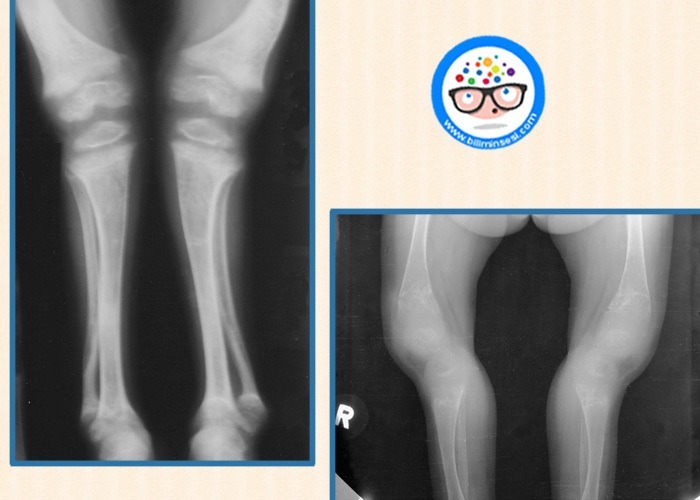

- Yürümede fark edilen bacak eğriliği

Belirtilerin görülmesinden sonra yapılacak ALP ölçümü, kan fosfor ve kalsiyum değerlerinin tespiti ve karşılaştırması ile kemik filmi raşitizmin bulunup bulunmadığını ortaya çıkarmaktadır.